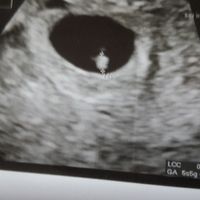

Prima eco 6+1

Vi presento il mio fagiolino di 2.4 mm... tutto cuore che pulsava forte a occhio nudo (lo sentiremo a 10 settimane). Da domani dieta ferrea....e sfilza di esami (circa 30 ) che vedrà il mio gine il...